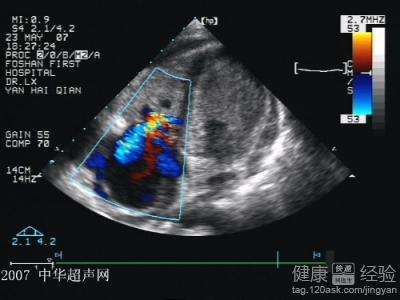

心肌病是指心肌出現功能障礙的心肌疾病,據病理生理學,將之為經典四型:擴張型,肥厚型,限制型,致心律失常型。其中限制型臨床少見,其解剖特點為:心室擴張受限,舒張容量下降,收縮正常,間質纖維化。症狀特點:初始:發熱、乏力;後繼心功能衰竭:心悸、呼吸困難、水腫、肝大、頸靜脈怒張、腹水;治療無特效方法,對症治療,心內膜剝脫術或心髒移植科考慮。

3輔助檢查結果:WBC升高,嗜酸性粒細胞增多;心電圖提示窦緩、低電壓、心防心室增大、心律失常,以房顫居多;心室壓力曲線早期下陷;心內膜增厚,心腔縮小;心肌活檢提示:心肌纖維化。